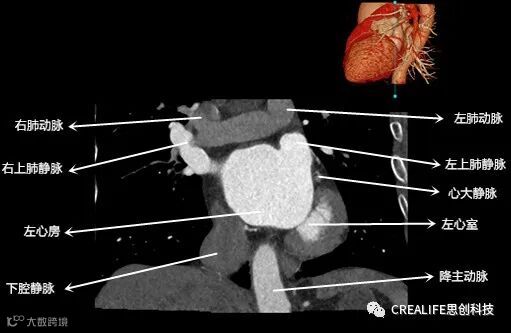

今天,跟大家分享心脏影像的经典层面——冠状位。通过冠状位的影像,我们可以从正位观察到心脏结构,看到主动脉的纵向剖面及冠窦交界处的心脏形态等多方位的心脏结构。现在,就让我们率先一睹“冠状位”的奇妙风采吧!

毋庸置疑,影像解剖学可为医师提供优良的诊断依据,包括瓣膜钙化程度、主动脉瓣环直径、主动脉窦直径及高度、冠状动脉开口高度、入径血管直径等关键数据,以此,为术前提供更全面的评估指标。